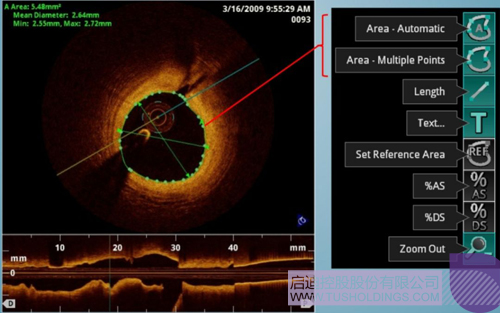

光学相干断层成像技术(OCT)是一种新型影像技术,它利用弱相干光干涉仪的基本原理,检测生物组织不同深度层面对入射弱相干光的背向反射或几次散射信号,通过扫描,可得到生物组织二维或三维结构图像。OCT由于具有极高的分辨率(10 um),可以对内膜性质和支架结构更加精确地辨别和分析。

在冠脉介入治疗迅猛发展的今天,随着复杂病变患者日益增多,血管内影像扮演了越来越重要的角色。OCT借助其高分辨率的图像优势,可以提供更清晰的病变特征和支架植入情况,OCT存在以下优势:可更精确的检测介入治疗后的血管内情况,如夹层、支架贴壁不良、组织脱垂等,另外,它在管腔直径和面积方面的测量精度更高。

血管腔内精准评估